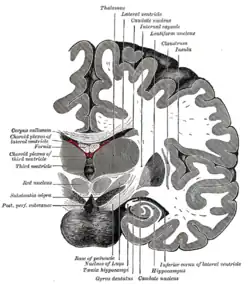

Coronal section of brain immediately in front of pons. -